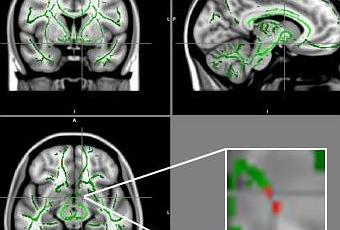

L'étude menée à l'Université de Sao Paulo au Brésil auprès de 59 adolescents obèses âgés de 11 à 18 ans et 61 adolescents témoins en bonne santé, appariés pour le sexe, l'âge, la catégorie socioéconomique et le niveau d'éducation a évalué chez ces participants l'intégrité de la substance blanche du cerveau par imagerie du tenseur de diffusion (DTI). Cette technique d'imagerie permet de mesurer l'anisotropie fonctionnelle (AF), le mouvement microscopique, ou l'anisotropie, des molécules d'eau à l'intérieur et autour des fibres de la matière blanche du cerveau. Les valeurs AF basses indiquent une plus grande perturbation dans la matière blanche.

Cette analyse révèle une perte d'intégrité de la substance blanche dans plusieurs zones du cerveau chez les jeunes patients obèses. Comparé à ceux de témoins en bonne santé, les cerveaux des adolescents obèses présentent une réduction des valeurs de l'AF dans plusieurs zones du cerveau dont l'amygdale, l'hippocampe, le thalamus, le gyrus cingulaire, le fornix, l'insula, le putamen, le gyrus orbitaire et l'hypothalamus bilatéral. Or, plusieurs de ces zones sont impliquées dans la régulation de l'appétit, le contrôle des impulsions, les émotions et la récompense et le plaisir de manger.